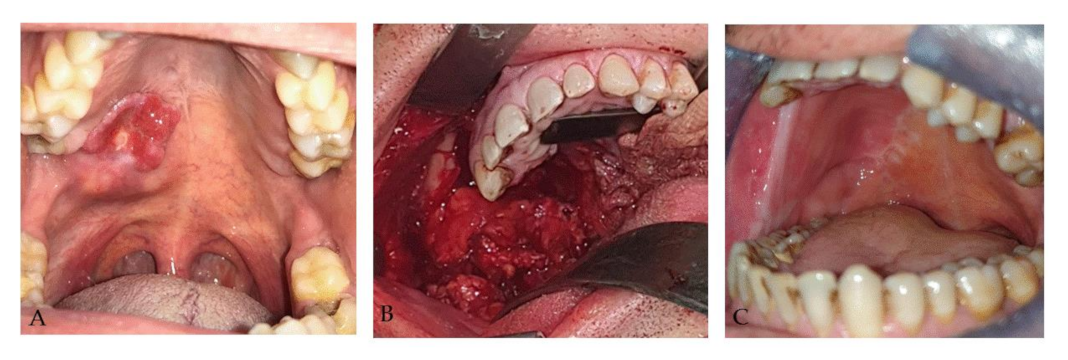

2.2. Case 2